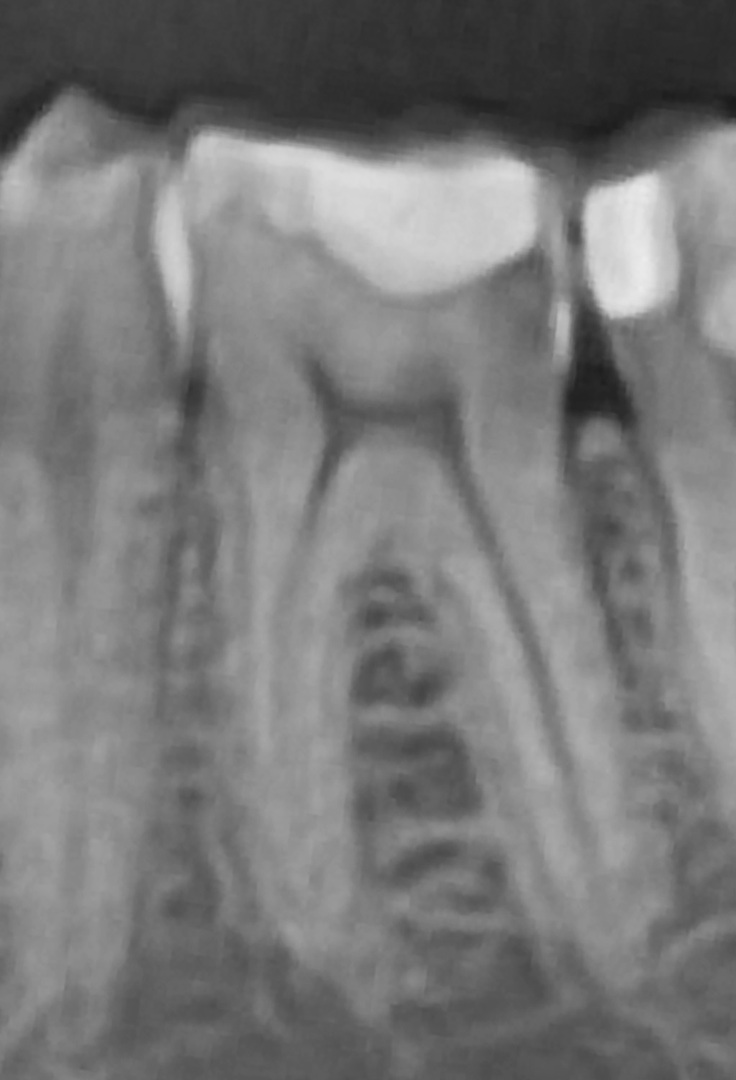

After try-in (Fig. 22), the restoration was bonded using a low-flow, highly filled composite (Estelite Universal Flow, SuperLow; Fig. 23). Excess material was removed (Fig. 24), followed by another round of light polymerisation for 20 seconds per side. Final excess removal was done (Fig. 25), and thanks to the preformed anatomy, most of the morphological detail remained intact even after occlusal adjustment (Fig. 26). A control radiograph was taken (Fig. 27).

Fig. 26: Occlusal view after final adjustment.